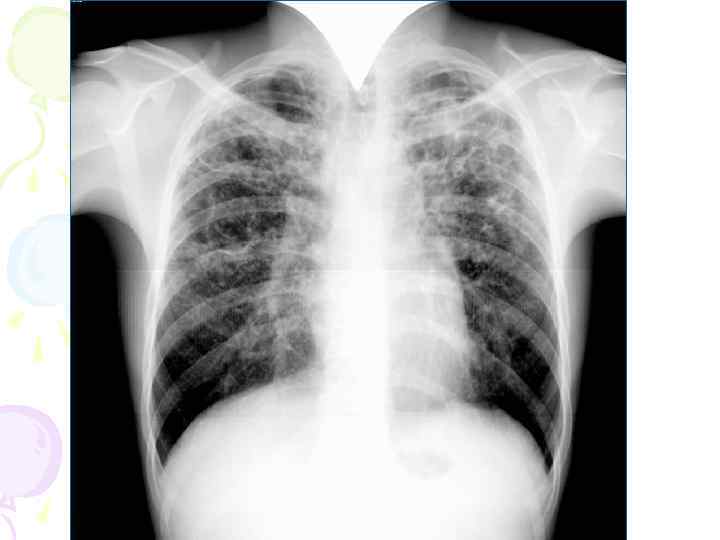

Рентгенологическая картина Спустя 10 -14 дней болезни появляются множественные мелкие / до 2 мм/ однотипные очаги на всем протяжении легких, создается впечатление о более массивной диссеминации в средних отделах. Очаги округлой формы, малой интенсивности, контуры нечеткие, часто расположены в виде цепочки вдоль сосудов. Сосудистый рисунок обеднен